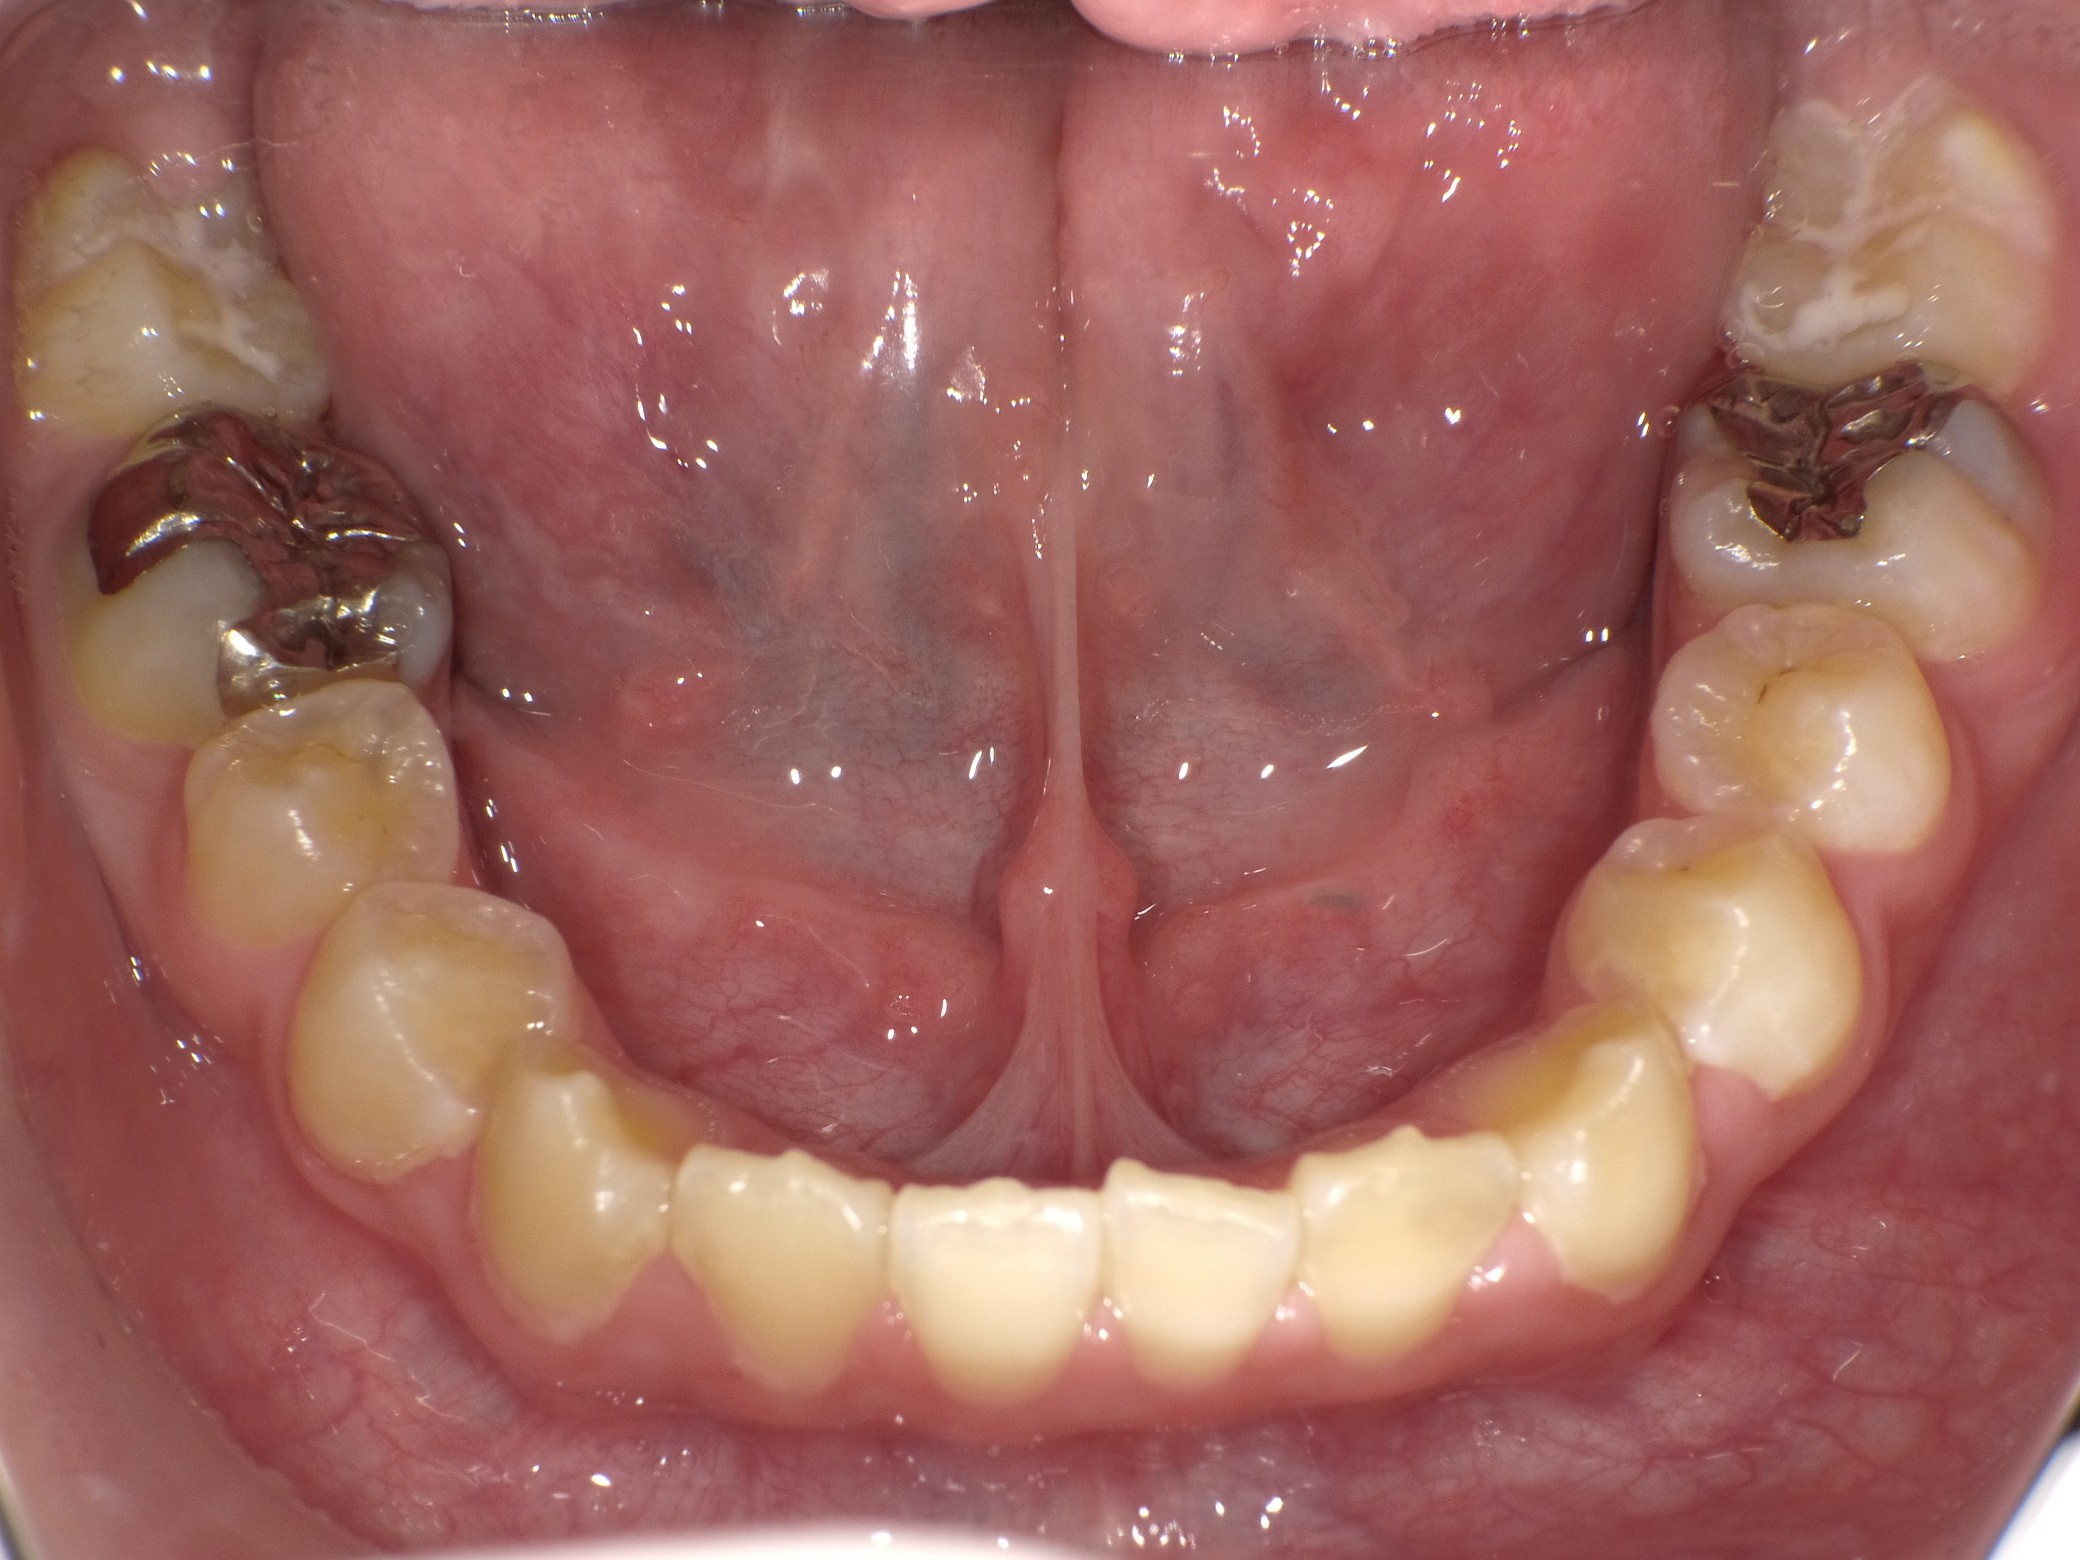

実際の症例

治療前です 下の奥歯が著しく崩壊しています

本来なら神経を取る治療を行うと思いますが、ドックスセメントにて神経の保護をはかりました

ドックスセメントを充填後です

経過を見たのち順次銀歯をはめていきました

自発痛などもなかったため経過は良好ですが、糖質制限や定期メンテナンスの継続が必須です